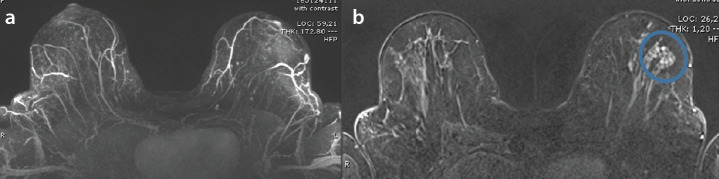

Purpose: This study aims to evaluate the effectiveness of the Kaiser score (KS) system in assessing breast lesions with uncertain malignant potential (B3).

Methods: Breast magnetic resonance imaging (MRI) scans from a total of 76 patients with histologically proven B3 lesions were included in this study. The KS was recorded for each MRI scan. The patients were classified based on biopsy results, and upgraded lesions were identified. Statistical analysis was conducted to evaluate the association between high KS values and upgraded lesions.

Results: The mean age of the 76 patients was calculated as 49.6 ± 10.1. A significant association was observed between the KS system and the prediction of malignancy upgrade (P < 0.001). Furthermore, among the descriptors, spiculation, margin, and upgrading prediction demonstrated a statistically significant difference (P < 0.001). Additionally, the specificity improved when the accepted KS cut-off value was set at seven instead of five. A significant association was also observed between the KS system and the papilloma upgrade rate within the B3 lesion subgroups (P < 0.001).

Conclusion: Breast radiology plays a crucial role in the diagnosis of B3 lesions. Our findings suggest that the KS system holds promise as a tool for predicting the upgrade potential of B3 lesions.

Clinical significance: This study demonstrated that the KS system may assist in predicting the upgrade potential of B3 breast lesions. It also demonstrated that spiculation and margin descriptors within the KS system possess a high positive predictive value for upgrade prediction. Additionally, we believe that the KS system can help prevent unnecessary surgeries in patients with B3 lesions.